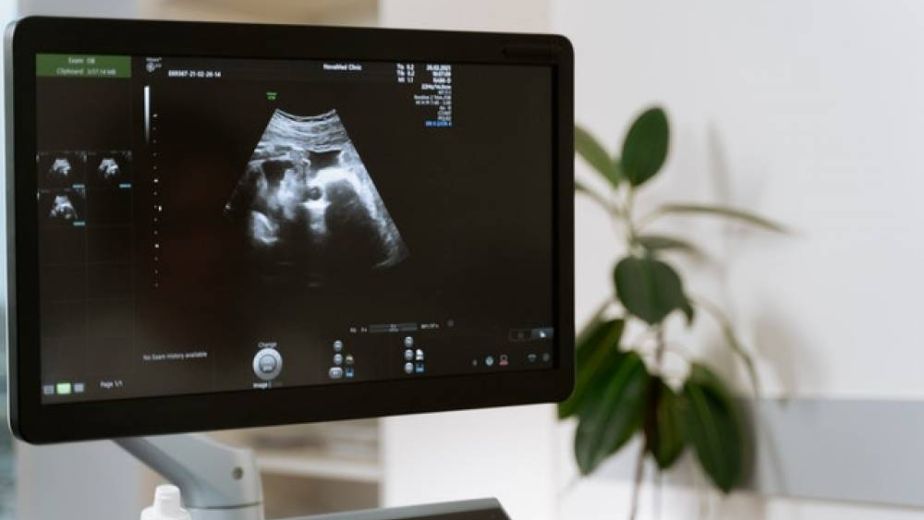

اشعة موجات فوق الصوتية والمعروفة أيضًا (بتخطيط الصَّدى) أو التّصوير بالموجات فوق الصّوتيّة (السونار)، عبارة عن إجراء فحصي و تشخيصي يتم عن طريق نشر موجات صوتيّة عالية التردد لا يمكن أن تسمعها الُأذن البشريّة عبر أنسجة الجسم ، ثم العمل على تسجيل الأصداء وتحويلها إلى صور فوتوغرافيّة أو تلفزيونيّة للتراكيب الدّاخلية للجسم تظهر علي شاشة كمبيوتر .

وتساعد صور اشعة موجات فوق الصوتية على تشخيص وفحص مجموعة واسعة من الأمراض والحالات الصحية ، حيث يتم استخدامها لتكوين صور للأنسجة اللينة أو الرخوة مثل المرارة والكبد والقلب والكلى والأعضاء التناسلية الانثوية ، وحتى للَأجِنة التي لا تزال موجودة في الرحم ، كما يمكن للموجات فوق الصوتية الكشف عن الانسدادات التي توجد في الأوعية الدّموية .

الاستخدام الأكثر انتشارا لجهاز الموجات فوق الصوتية هو في حالات الحمل، حيث يتم تصوير الأجنة بغرض :

التأكد من وجود الجنين بشكل سليم

تحديد وجود أكثر من جنين في دورة الحمل الواحدة

متابعة مراحل الحمل جميعها والتأكد باستمرار من سلامة الجنين.

تشخيص وتحديد بعض الحالات غير الطبيعية كالتشوهات البدنية في الأجنة.